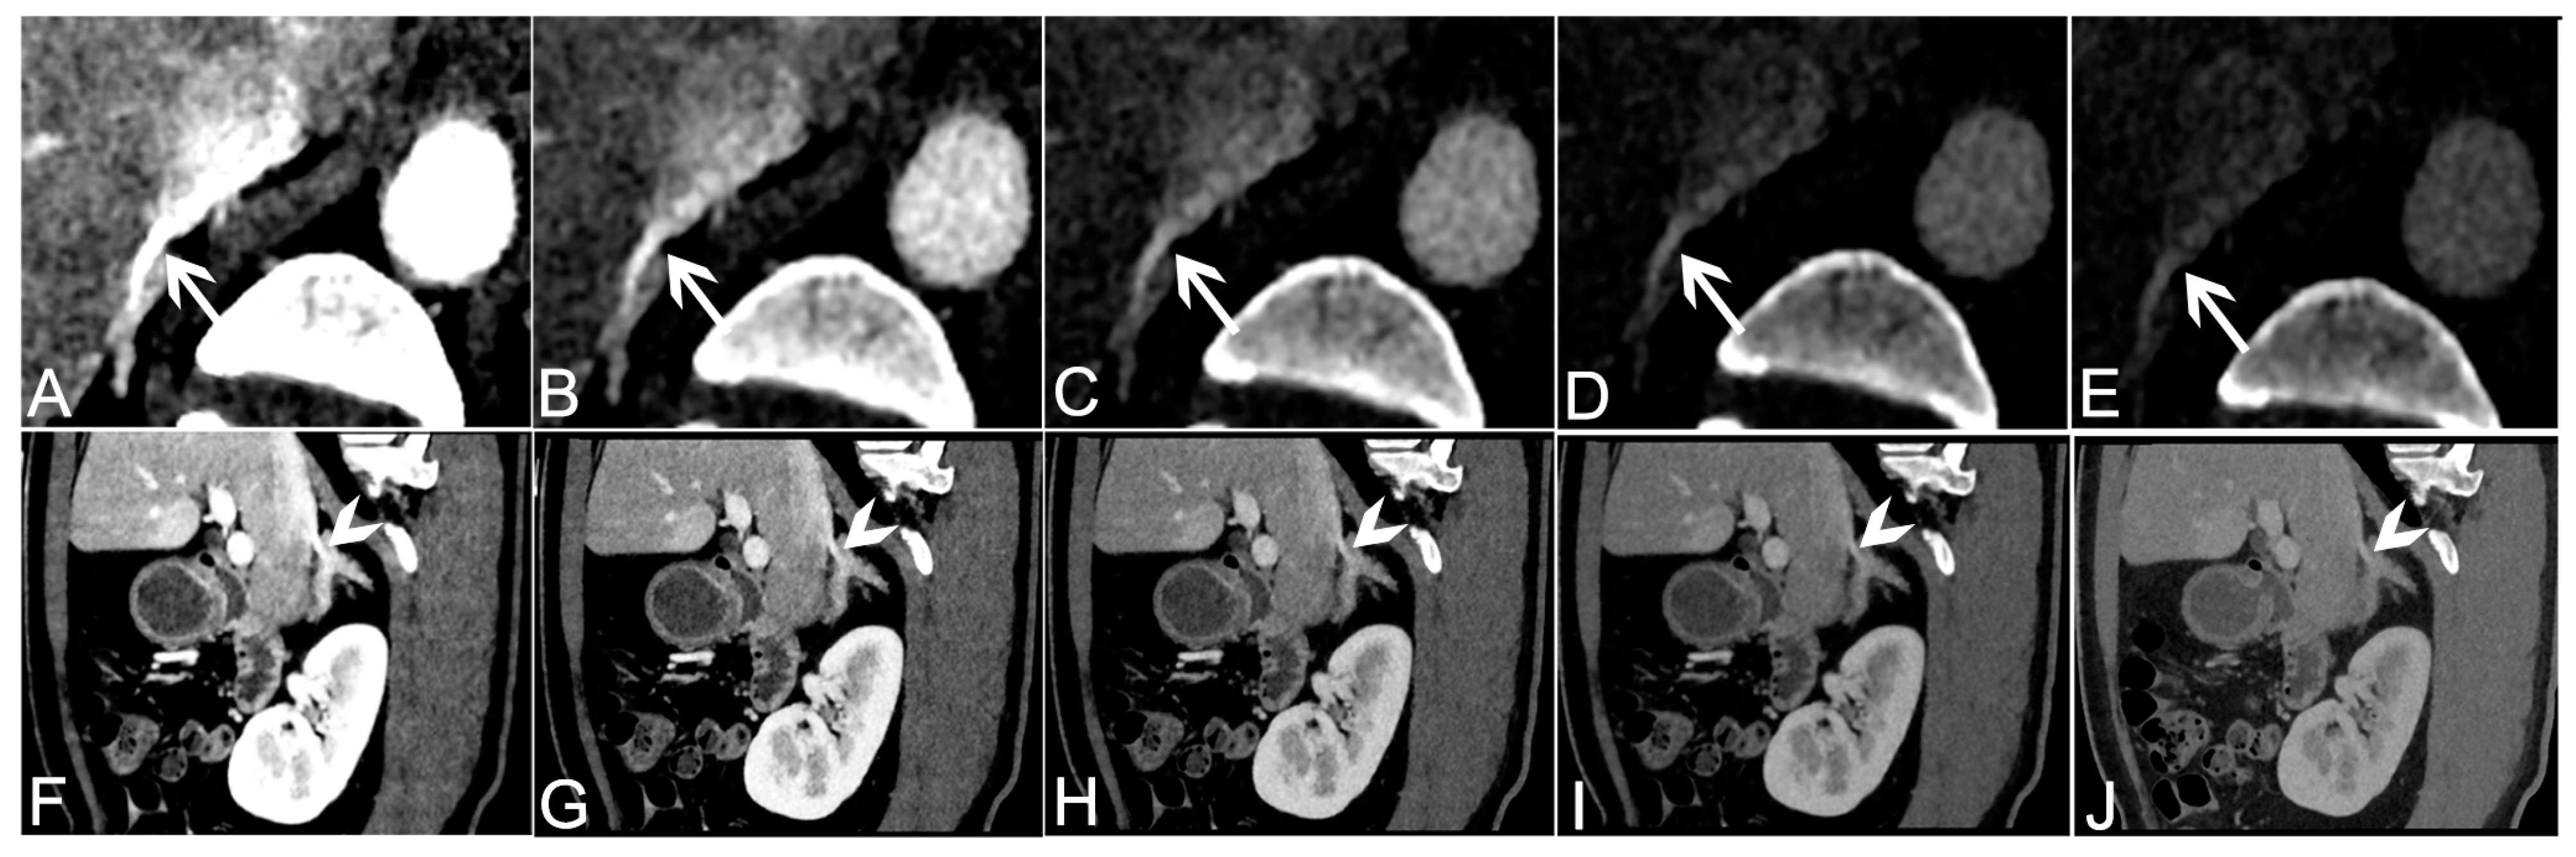

2.5. DECT Subjective Image Analysis

3.3. Subjective Analysis of VMI+ Series from Venous Phase Data